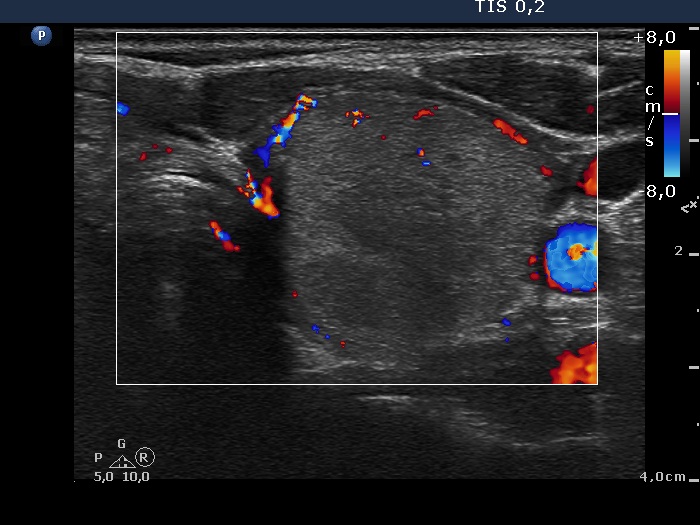

Ethanol sclerotherapy: non-toxic solid nodules - Case 5

Twelve years after the therapy (ultrasonographic picture 8)

Left lobe, horizontal section, color Doppler mode. The nodule presents perinodular blood flow.